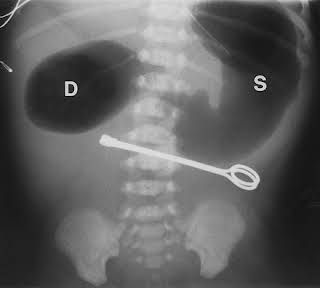

Cause : * congenital obstruction * duodenal web * duodenal atresia * duodenal stenosis * annular pancreas * midgut volvulus * external compression of the duodenum * choledochal cyst * mesenteric duplication cyst * intramural duodenal hematoma * preduodenal portal vein * retroperitoneal tumor * superior mesenteric artery syndrome